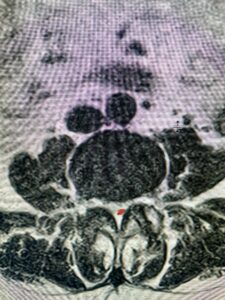

This 54-year-old morbidly obese female presents with progressive back and leg pain and quadriceps weakness. She had no diabetes. She failed all means of conservative management including physical therapy and epidural injections. On imaging she had severe stenosis at L3-4 with a disc protrusion and a slight grade 1 spondylolisthesis at L3-4 (Fig 1). We performed dynamic lumbar x-rays which demonstrated instability at L3-4 and L4-5 (Fig 2). The patient wished to have surgery. We performed an L2-4 decompressive laminectomy and L3-5 in situ fusion because of her instability. Post operatively the patient had relief of leg pain, although the patient was slow to mobilize.

Figs. 1a: Sagittal lumbar T2-weighted MRI demonstrating severe lumbar stenosis with a slight grade 1 at L3-4 and a disc protrusion (red arrow )

Fig 1b: Axial lumbar T2-weighted MRI demonstrating severe lumbar stenosis (red dot)